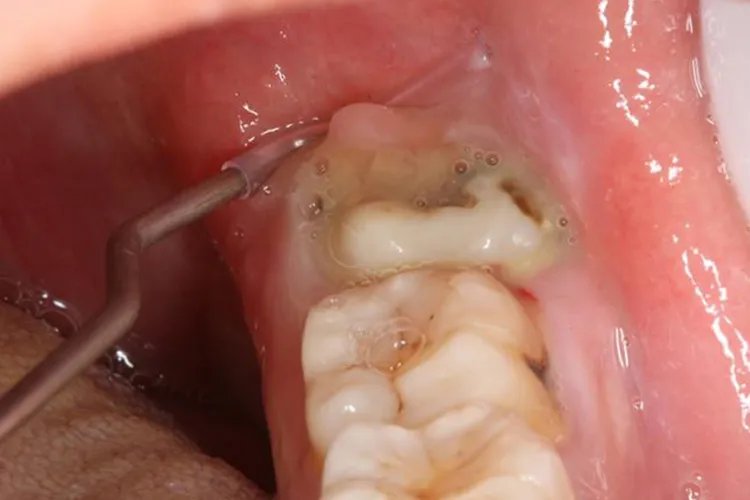

智齿冠周炎急性智齿冠周炎末期未彻底治愈可转变为慢性过程,临床表现为冠周软组织轻度水肿,龈袋内可有少量脓性分泌物,出现溃烂。如果发生在面颊部可有慢性瘘管形成,瘘管口会有红色的肉芽组织,全身可伴有低热。